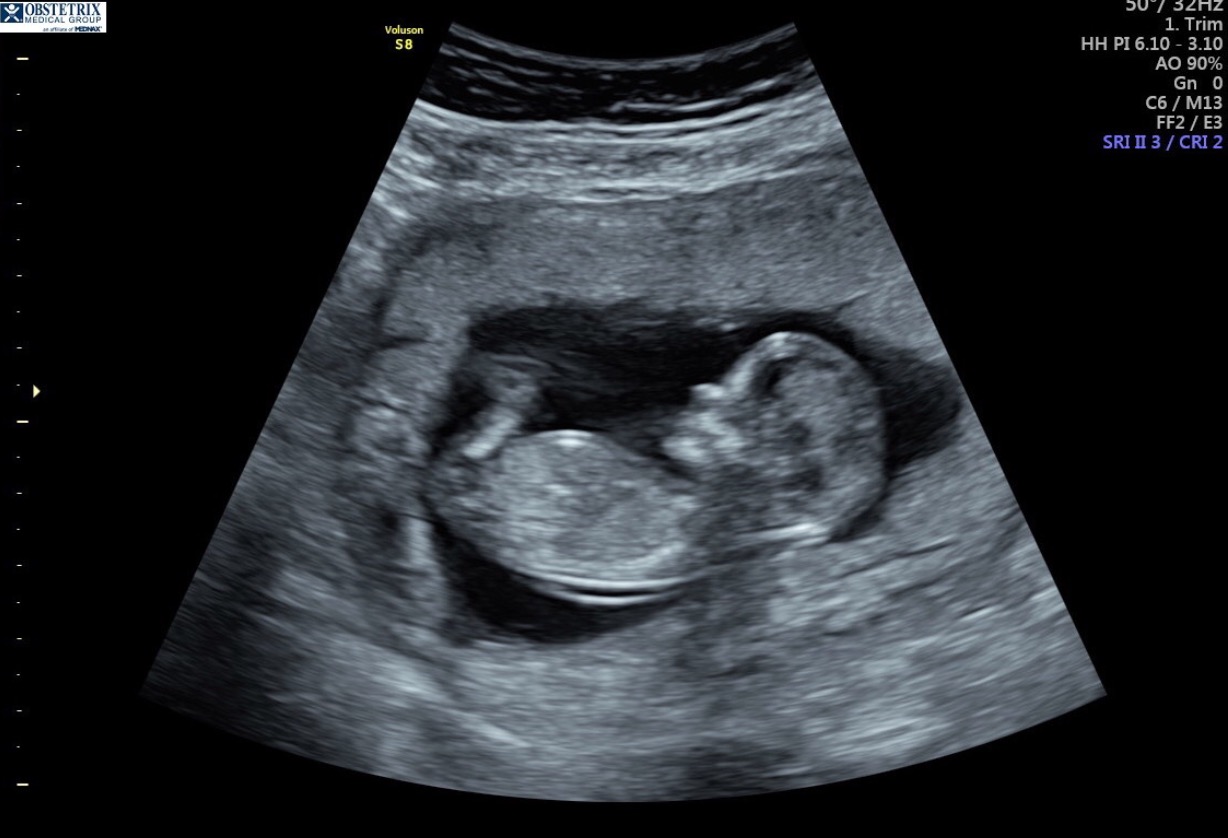

Everyone on my pregnancy app thinks this is a boy due to the skull. Any possibility of girl still?? After 4 boys, I am praying! The cord was between the legs the whole time so we didn't get a nub look or picture :( 12 weeks and 5 days